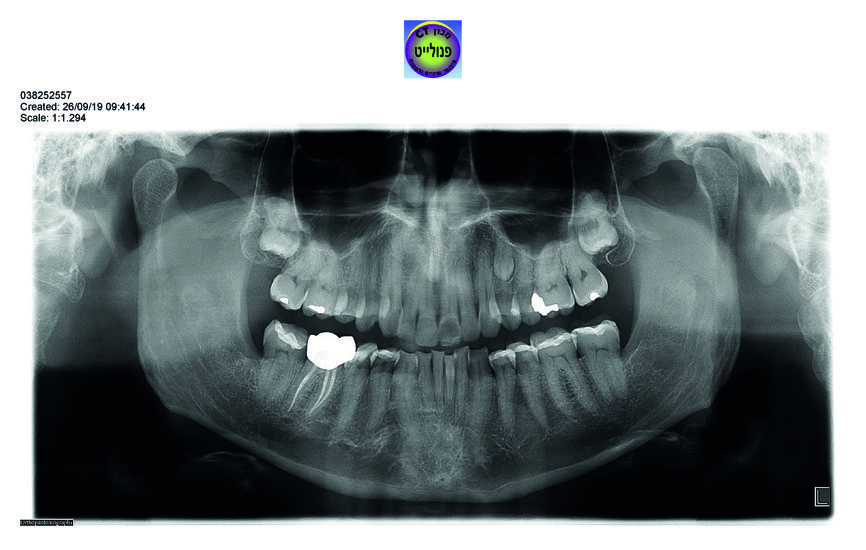

Examen radiographique

– La radio panoramique8

met en évidence la présence de deux dents de sagesse incluses (18 et 28), l’agénésie des 38 et 48 et la présence d’un odontome au niveau de la 24. On devine par ailleurs sur le cliché les overlays des dents 34, 35, 37, 44–47. La dent 46 présente un traitement endodontique très satisfaisant, et une coiffe prothétique parfaitement adaptée. On devine l’abrasion importante des incisives mandibulaires qui a motivé la première consultation de notre patient l’année précédente.